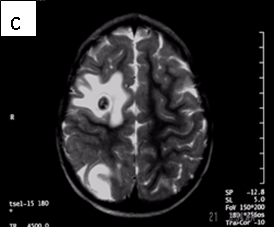

Figure 1: Neurocysticercosis in an 18-month child. a. Sagittal T1 without gadolinium; b. Axial T1 with gadolinium; c. Axial T2; d. Coronal FLAIR

Radiologic diagnosis: Neurocysticercosis.

| MRI | Live forms have a characteristic appearance: fluid-filled lesions containing an inverted scoleces, surrounded by thin low-signal capsule. They do not stimulate inflammation and do not enhance; dying forms do. In the less common racemose type, the cysts may be hard to see because they have similar imaging features as the CSF. |

For cysts that cause symptoms outside the CNS, surgical resection achieves cure. The treatment of symptomatic neurocysticercosis, which carries a 50% mortality rate, is more problematic. Two drugs, albendazole and praziquantel control symptoms and cause regression in the size and number of cysts in patients with viable (non-enhancing) cysts in their brain parenchyma. However, they provide limited improvement in patients with arachnoiditis and none in patients with intraventricular cysts. These latter patients should be treated with surgery or palliated with ventricular shunting, anticonvulsants, and anti-inflammatory drugs. According to our case’s physician, he did not receive anti-parasitic medication because the imaging features suggested that the parasites were dying (vasogenic edema and ring enhancement) (6).